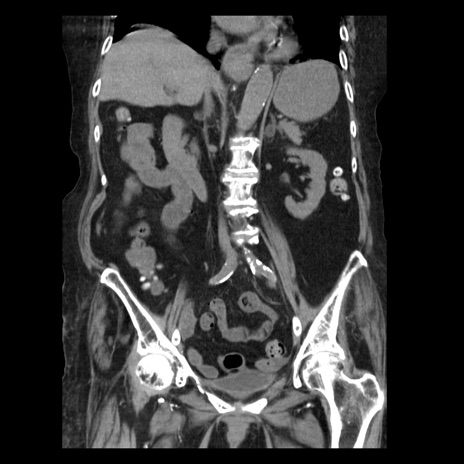

症例14(冠状断像)

【症例】 90歳代女性

【主訴】 腹痛・嘔吐

【現病歴】今朝から左側腹部痛を認めた。 経過観察していたが、嘔吐を認めたため来院。

【既往歴】 子宮癌術後

【身体所見】 意識清明、BP 127/54mmHg、P 98bpm Sp02 95%(RA)、BT 35.8°C、腹部平坦・軟腸ぜん動音聴取良好、右下腹部圧痛(+) 反跳痛なし

【データ】WBC 9800、CRP 0.46